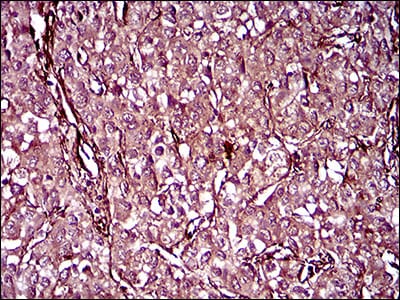

分类: 科研抗体货号: 30486P别名: ERBB; HER1; mENA; ERBB1; PIG61应用: WB,IHC,FCM反应种属: Human

分类: 科研抗体货号: 30486A别名: ERBB; HER1; mENA; ERBB1; PIG61应用: WB,IHC,FCM反应种属: Human